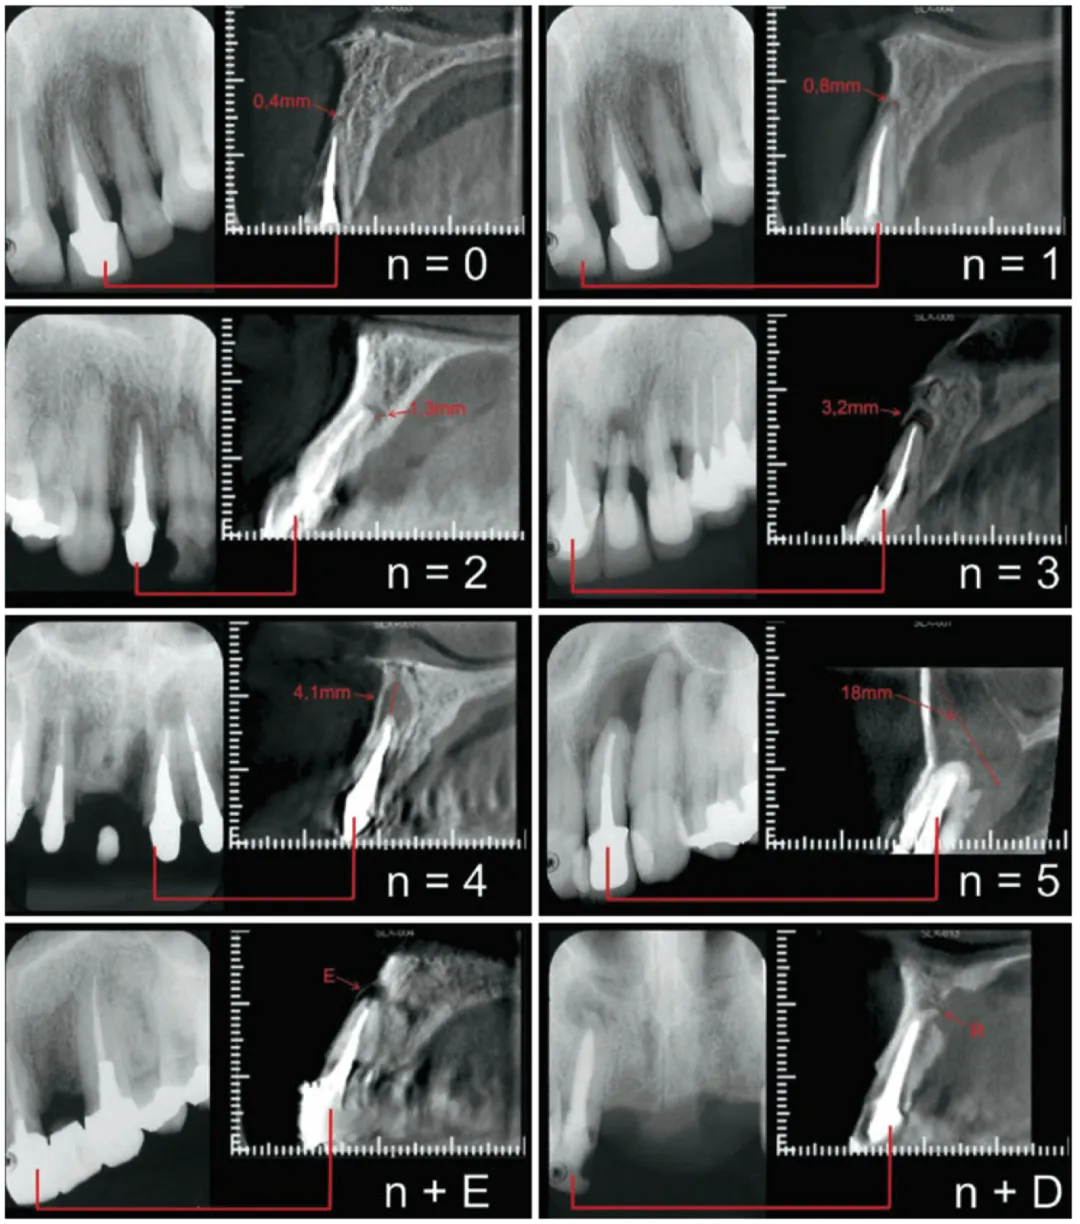

• 可使用根尖周指数 PAI 作为影像学评估的视觉分类系统

<<  滑动查看下一张图片  >>